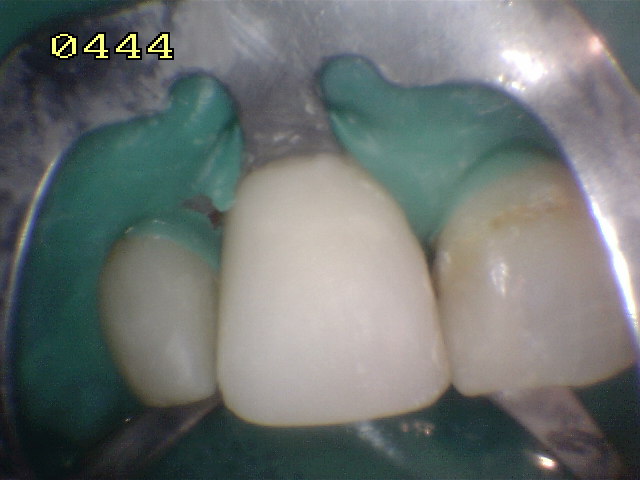

Microabrasión con acido

ortofosfórico y pomez |

Caso terminado con

resina de fotocurado A2 |